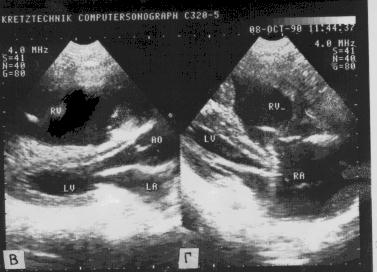

Двухмерная ЭхоКГ (рис.140):

Рис.140

- "Вдавливание" перегородки в полость левого

желудочка в парастернальной проекции длинной и поперечной оси сканирования.

- Дилатация ствола легочной артерии.

- Дистолическое выбухание створок клапана в выходной

тракт правого желудочка.